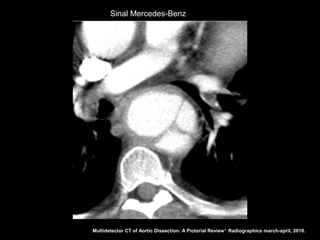

Sinal Mercedes-Benz

Sinal Mercedes-Benz Multidetector CTof Aortic Dissection: A Pictorial Review 1. Radiographics march-april, 2010.